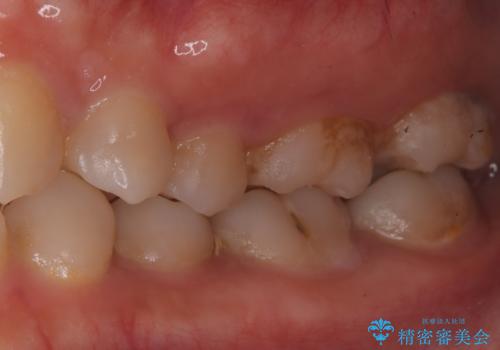

- 昨日からのズキズキとした激しい痛みを主訴にご来院されました。レントゲンおよび歯髄診察の結果、不可逆性の歯髄炎(歯の神経の重度の炎症)と診断。歯を残すことを第一に、まず痛みの原因である神経を取り除く根管治療を提案しました。また、虫歯が歯肉の下まで深く進行していたため、根管治療後に歯周外科処置を行い、最終的に精密なセラミッククラウンで修復する、総合的な治療計画を立案しました。

治療はまず、根管治療から始め、感染した神経を徹底的に除去することで、痛みをすぐに解消しました。再発を防ぐため、ラバーダムや顕微鏡を使って、根管内を丁寧に、そして精密に処置しました。次に、深い部分の虫歯を確実に治療するため、歯周外科処置を行い、治療しやすい環境を整えました。最後に、機能と見た目に優れたセラミッククラウンを作製・装着。根管治療から外科処置、審美修復までを一貫して行うことで、再発リスクの低い、長期的に安定して使える奥歯を取り戻していただけました。